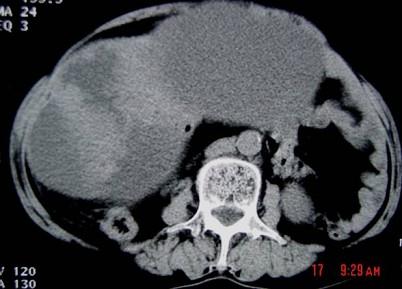

问题 55岁女性患者,腹胀腹痛消瘦一年余,行CT扫描如图所示,你认为最佳答案是 ( )

选项 A、卵巢浆液性囊腺瘤 B、卵巢囊腺癌 C、卵巢囊肿 D、卵巢粘液性囊腺瘤 E、卵巢表皮样囊肿

答案 B